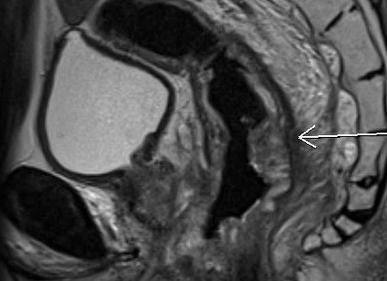

Квантовая физика, математика, биология, криогеника, химия и электроника сплелись единым узором, чтобы воплотиться в железе и показать настоящий внутренний мир человека, и даже, ни много ни мало, прочитать его мысли. Электроника таких аппаратов, по надежности и сложности может сравниться разве что с космической. Эта статья посвящается оборудованию и принципам работы магнитно-резонансных томографов. В области современного томографостроения лидируют мастодонты электронного мира: Siemens, General Electric, Philips, Hitachi. Только такие крупные компании могут позволить себе разработку столь сложного оборудования, стоимость которого как правило составляет десятки (почти сотни) миллионов рублей. Разумеется, ремонт такой дорогущей техники у официального представителя влетает в огромную копеечку владельцу аппарата (а они к слову в основном частные, а не государственные). Но не стоит отчаиваться! Также как и сервис-центры по ремонту ноутбуков, телефонов, чпу-станков, да собственно любой электроники существуют фирмы, занимающиеся ремонтом медицинского оборудования. В одной из таких фирм я и работаю, поэтому продемонстрирую вам интересную электронику и постараюсь описать ее функционал понятными словами. Подробнее ...